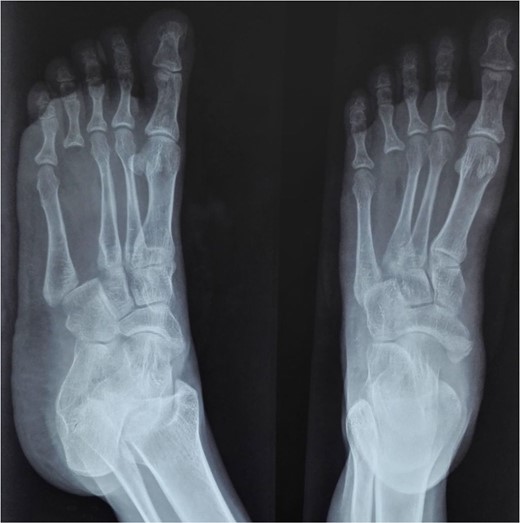

At 2 years postoperatively, the patient showed excellent functional outcomes. Radiographs demonstrated a stable MCP joint with well-preserved joint space, indicating successful graft incorporation (Fig. 3). Donor site radiographs at 2 years showed appropriate spacing between the third and fifth metatarsals with no evidence of arch collapse or stress reaction in the adjacent bones (Fig. 4). The patient achieved an active MCP joint range of motion of 0–80 deg (Fig. 5).